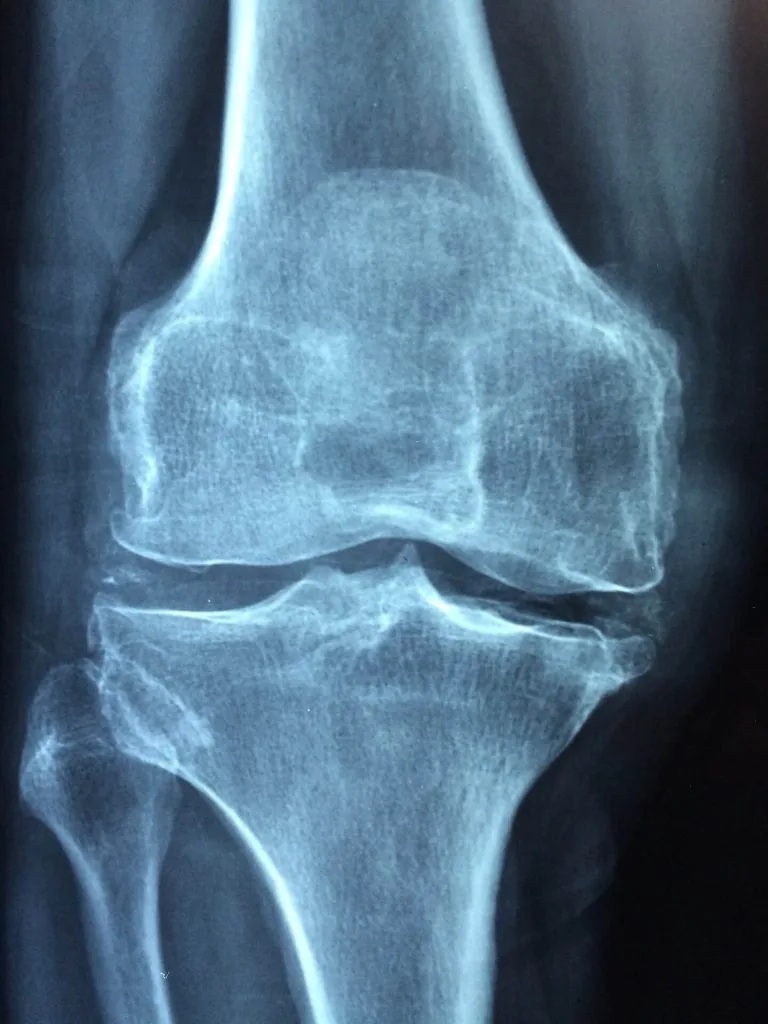

Knee Replacement Femur Fracture Treatment Recently, a case report was published describing a knee replacement as a possible treatment for a serious femur fracture. A…